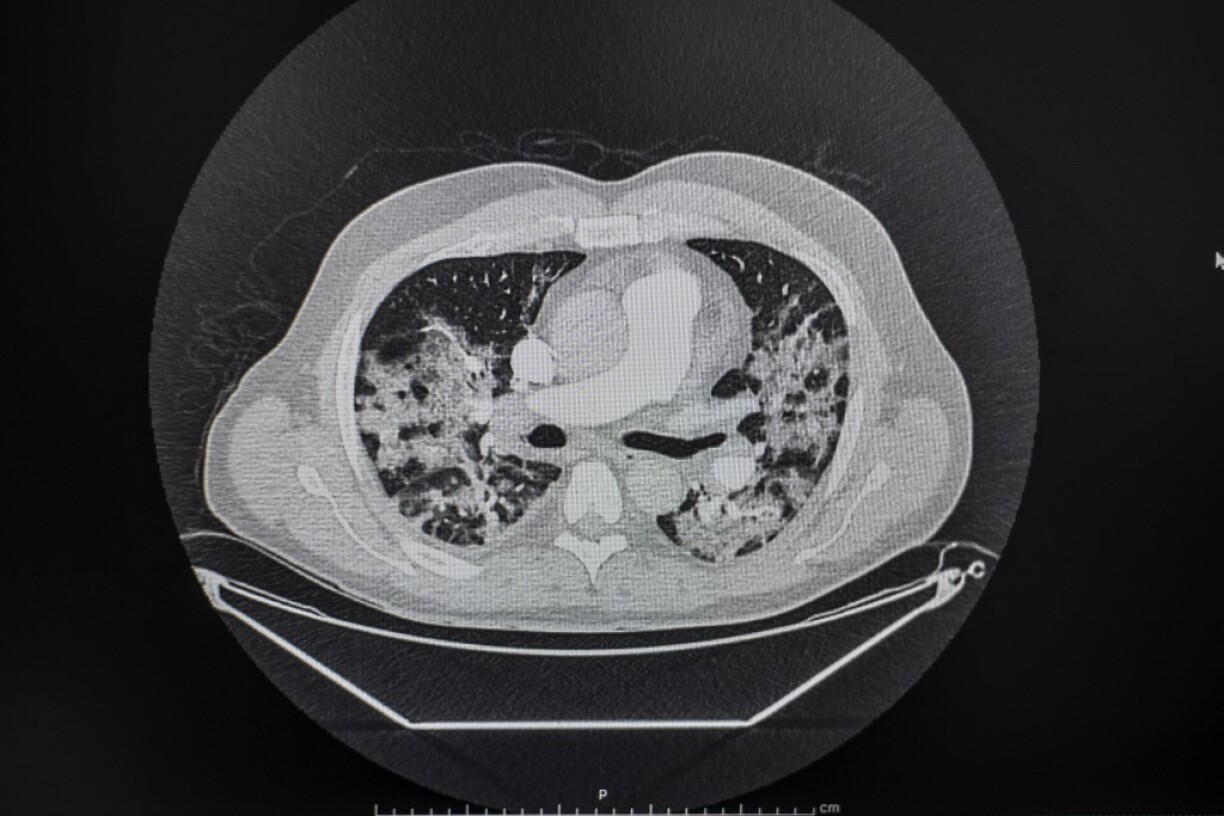

All images showing suspected Covid-19 infections were reviewed by two more radiologists, before they confirmed that the first case of the novel coronavirus appeared on 16 November.